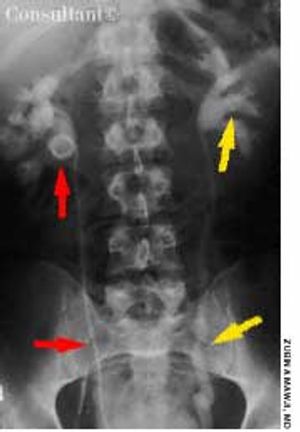

For 3 days, a 30-year-old man had had bilateral flank pain that radiated to the lower abdomen; gross hematuria had accompanied the pain for 1 day.